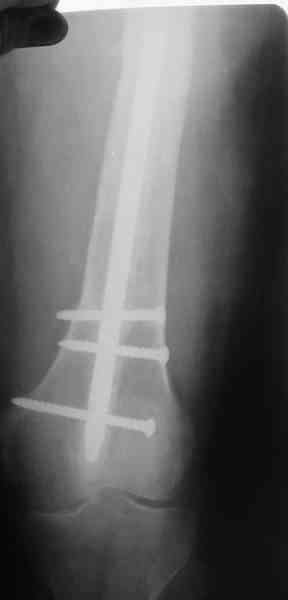

В настоящее время наш пациент ( см. http://weborto.net/forum/1177351385/) ходит с одним костылем. У него периодически открывается свищ на задне-наружной поверхности бедра с умеренным серозно-гнойным отделяемым. Температура тела и анализы нормальные. На рентгенограммах имеются признаки консолидации ложного сустава.

1, 2, 3, 4 - рентгенограммы бедра от 8 августа этого года (через четыре месяца после операции);